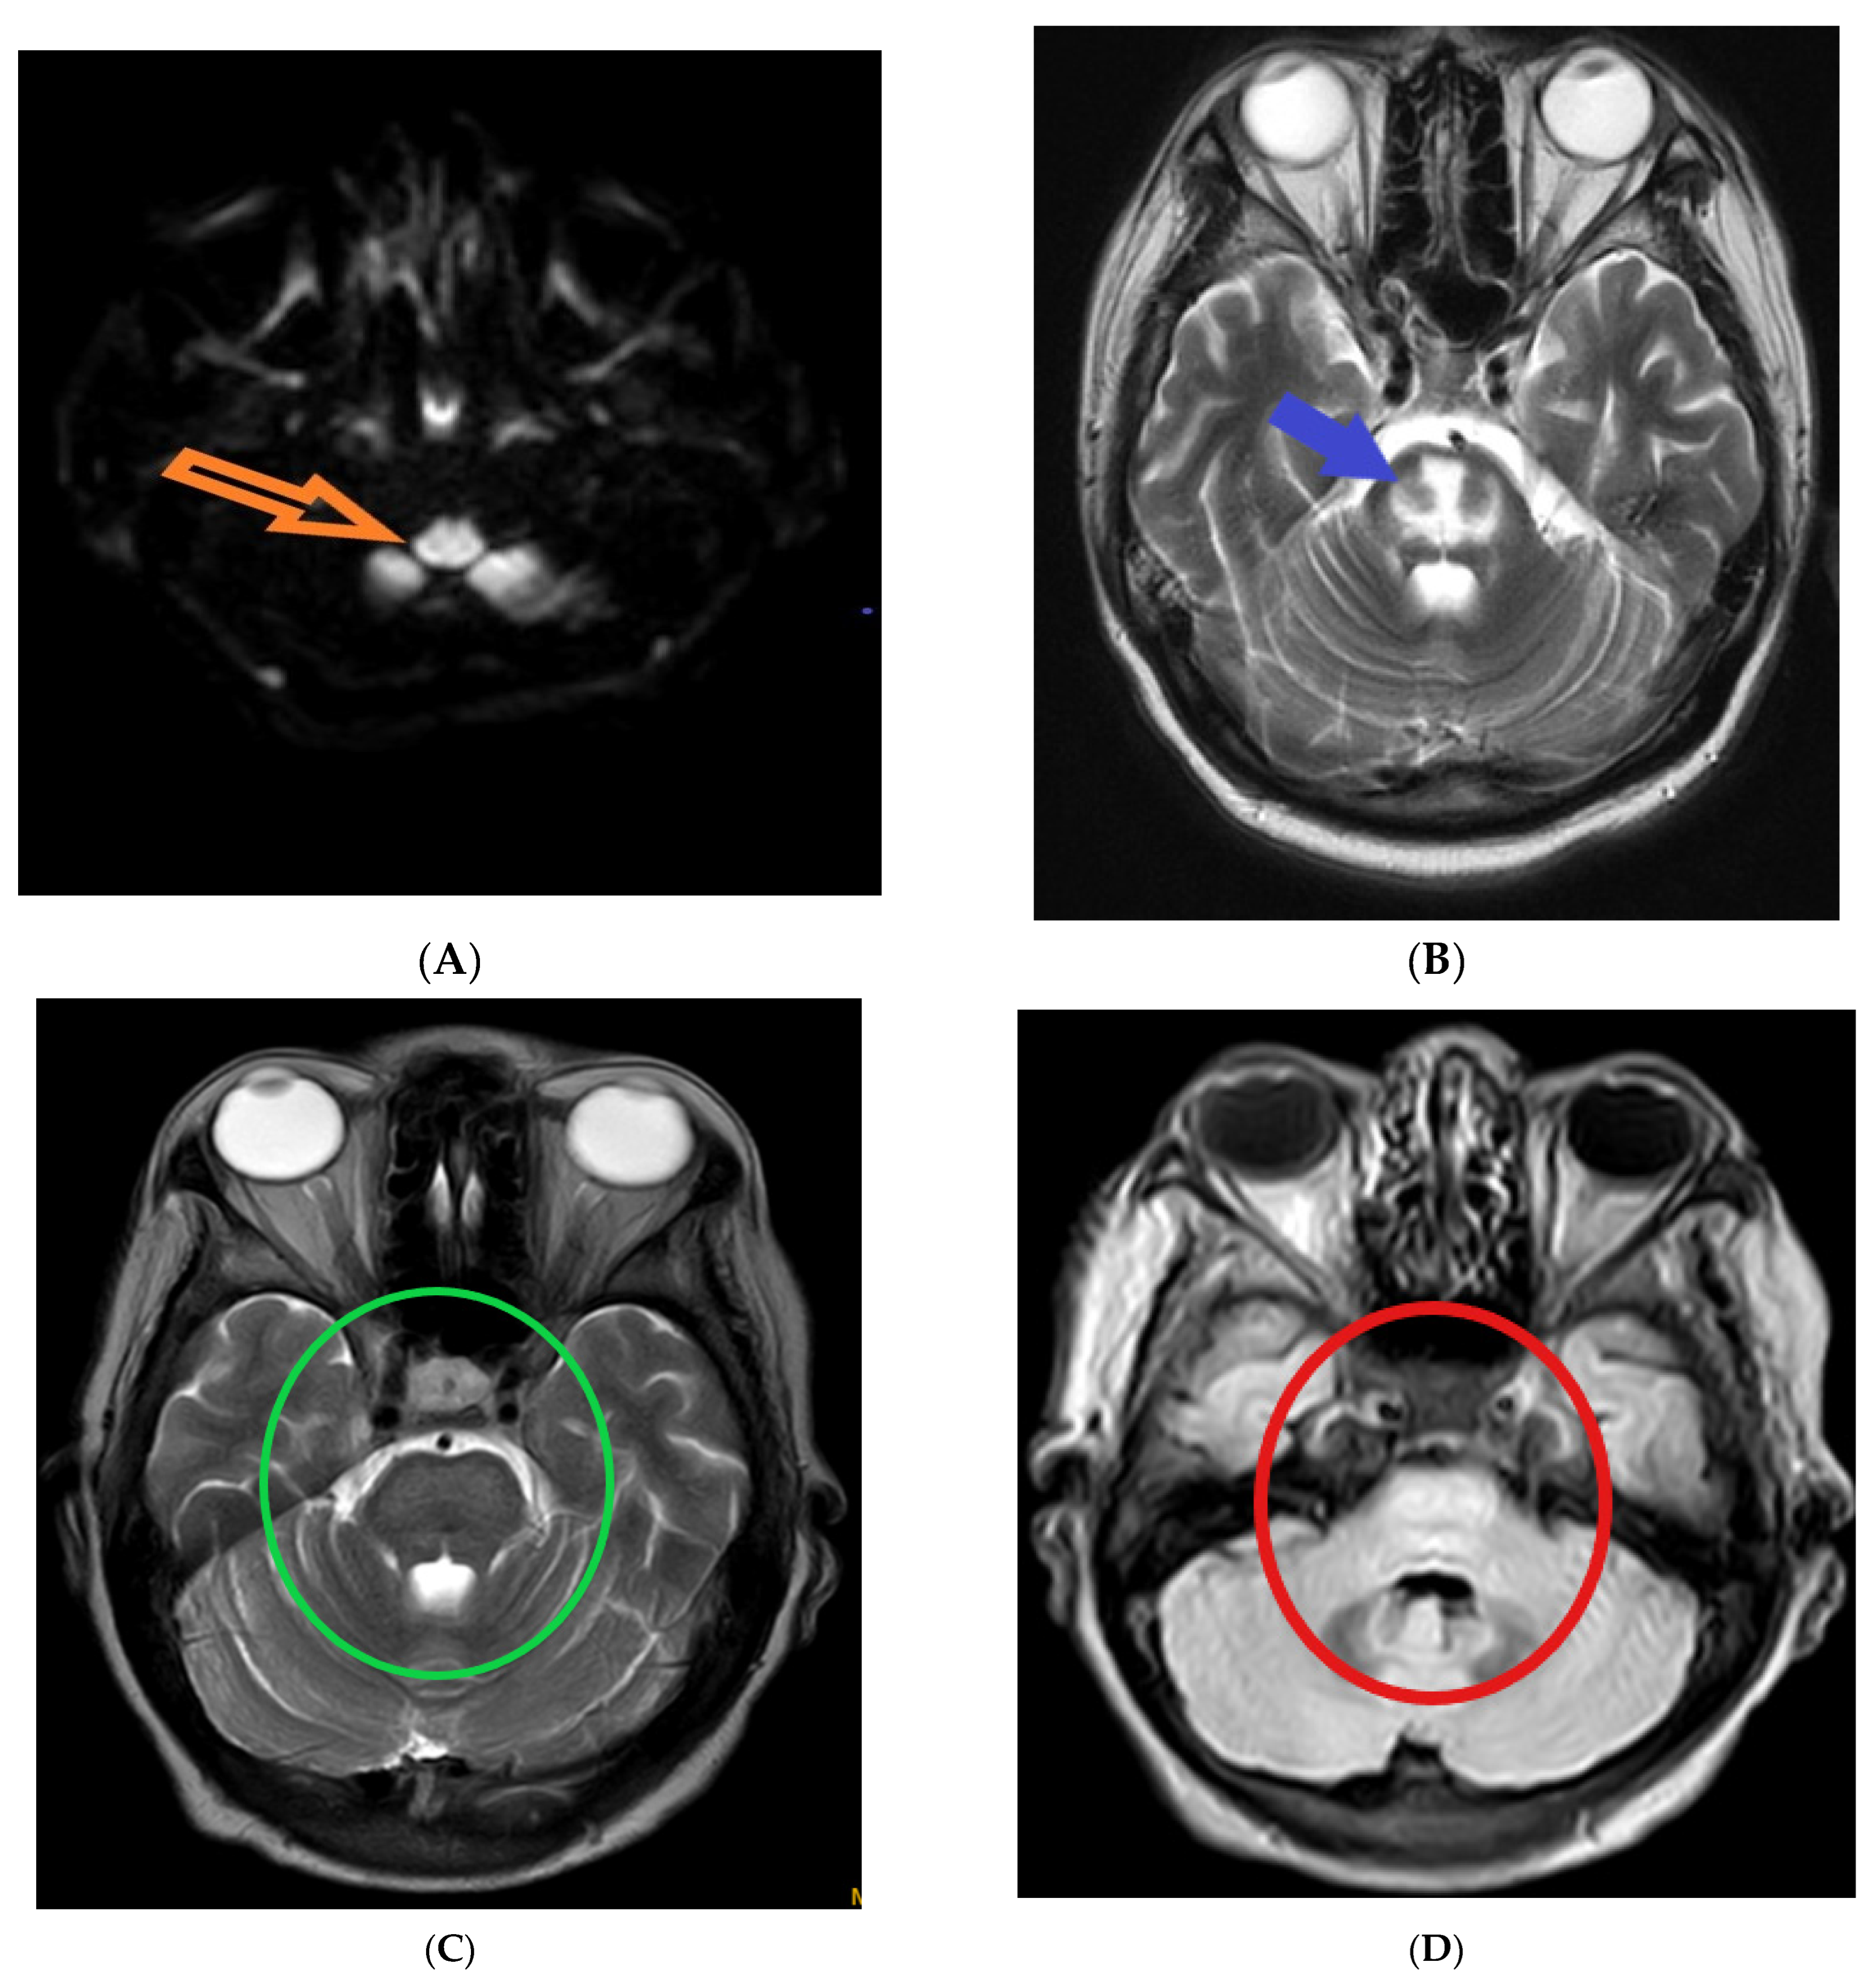

The following magnetic resonance imaging (MRI) images displaying different indicators observed in osmotic demyelination syndrome (Figure 1).

Figure 1.

Magnetic resonance imaging: (A) hyper-intensity of central pons in diffuse weighted image (orange arrow) [1]; (B) trident-shaped appearance (omega sign) of central pons in T2 weighted image (blue arrow) [2]. The characteristic “trident”-shaped appearance is attributed to the primary affectation of the transverse pontine fibres and the relatively limited involvement of the descending corticospinal tracts [3]; (C,D) piglet sign appearance of upper pons in T2 and FLAIR images (green and red circles, respectively) [4]. T2-weighted MR images exhibit a distinctive pattern known as the "piglet face" sign, initially described by Wagner et al. [5]. In this sign, the pons takes on a distinctive resemblance to the snout of a piglet, while the internal carotid arteries (ICAs) and the fourth ventricle together form the eyes and mouth, respectively, of the piglet-like configuration.